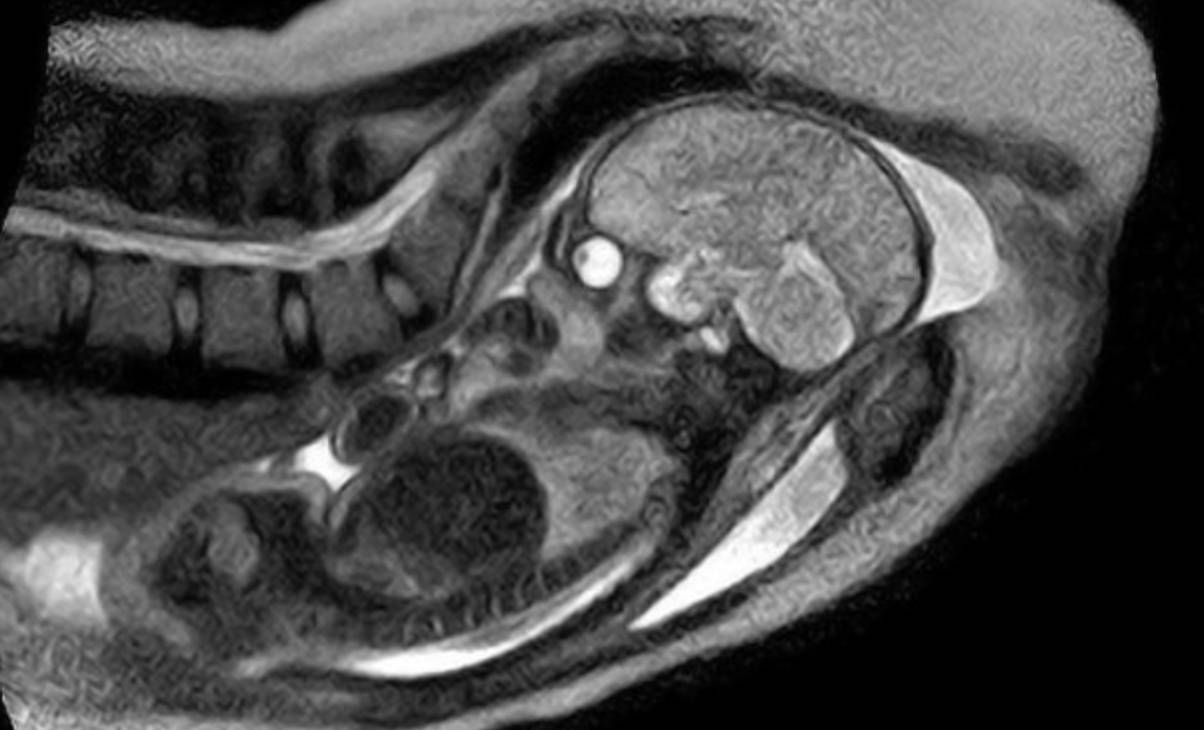

In 2010, a German girl welcomed her child from throughout the machine, with 3D photos of her womb being captured the entire time.

Amazingly, medical doctors might even watch how the infant’s head modified form as they moved from the beginning after which down the beginning canal in direction of the doorway to the vagina.